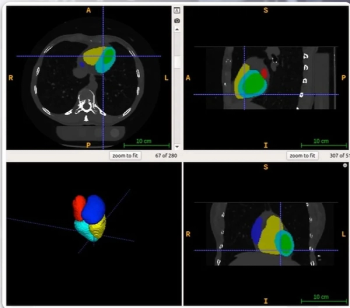

Emphasizing multi-structure segmentation and feature extraction from chest CT scans, an emerging AI model demonstrated an approximately 70 percent AUC for predicting significant incidental extrapulmonary findings as well as two-year and 10-year all-cause mortality.